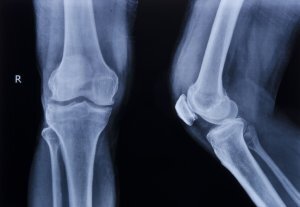

¿Cómo se clasifican las fracturas óseas?

Las fracturas óseas se clasifican según varios criterios:

Desplazadas o no desplazadas

Cuando se te rompe un hueso, los extremos rotos pueden permanecer alineados. Esto ocurre en una fractura no desplazada.

Pero si se aplica suficiente fuerza, los extremos fracturados se desalinean. Este tipo de fractura, denominada fractura desplazada, requiere un tratamiento adicional antes de que los médicos puedan poner un yeso o una férula en la lesión.

Concretamente, los médicos deben realinear los huesos en una fractura desplazada mediante manipulación externa o cirugía. Dependiendo de la localización y la naturaleza de la fractura, los médicos pueden incluso tener que utilizar tornillos y placas para mantener los fragmentos óseos alineados, de modo que puedan curarse.

Forma

Algunas fracturas se definen por su forma. Estas fracturas también se clasifican según si el hueso se desplaza o rompe la piel. Una fractura abierta con desplazamiento simple describe la forma, el desplazamiento y si ha roto la piel.

A continuación se enumeran algunas formas de fracturas:

- Una fractura transversal cruza el eje del hueso

- Una fractura en espiral rodea el eje del hueso

- Una fractura impactada se produce cuando el hueso se comprime longitudinalmente

- Una fractura conminuta se produce cuando el hueso se rompe en al menos tres partes

- Una fractura por avulsión se produce cuando un ligamento o tendón se desprende de un trozo de hueso al que estaba unido

Estas formas pueden afectar a si necesitas cirugía para reparar la fractura y a cuánto tardará en curarse el hueso.